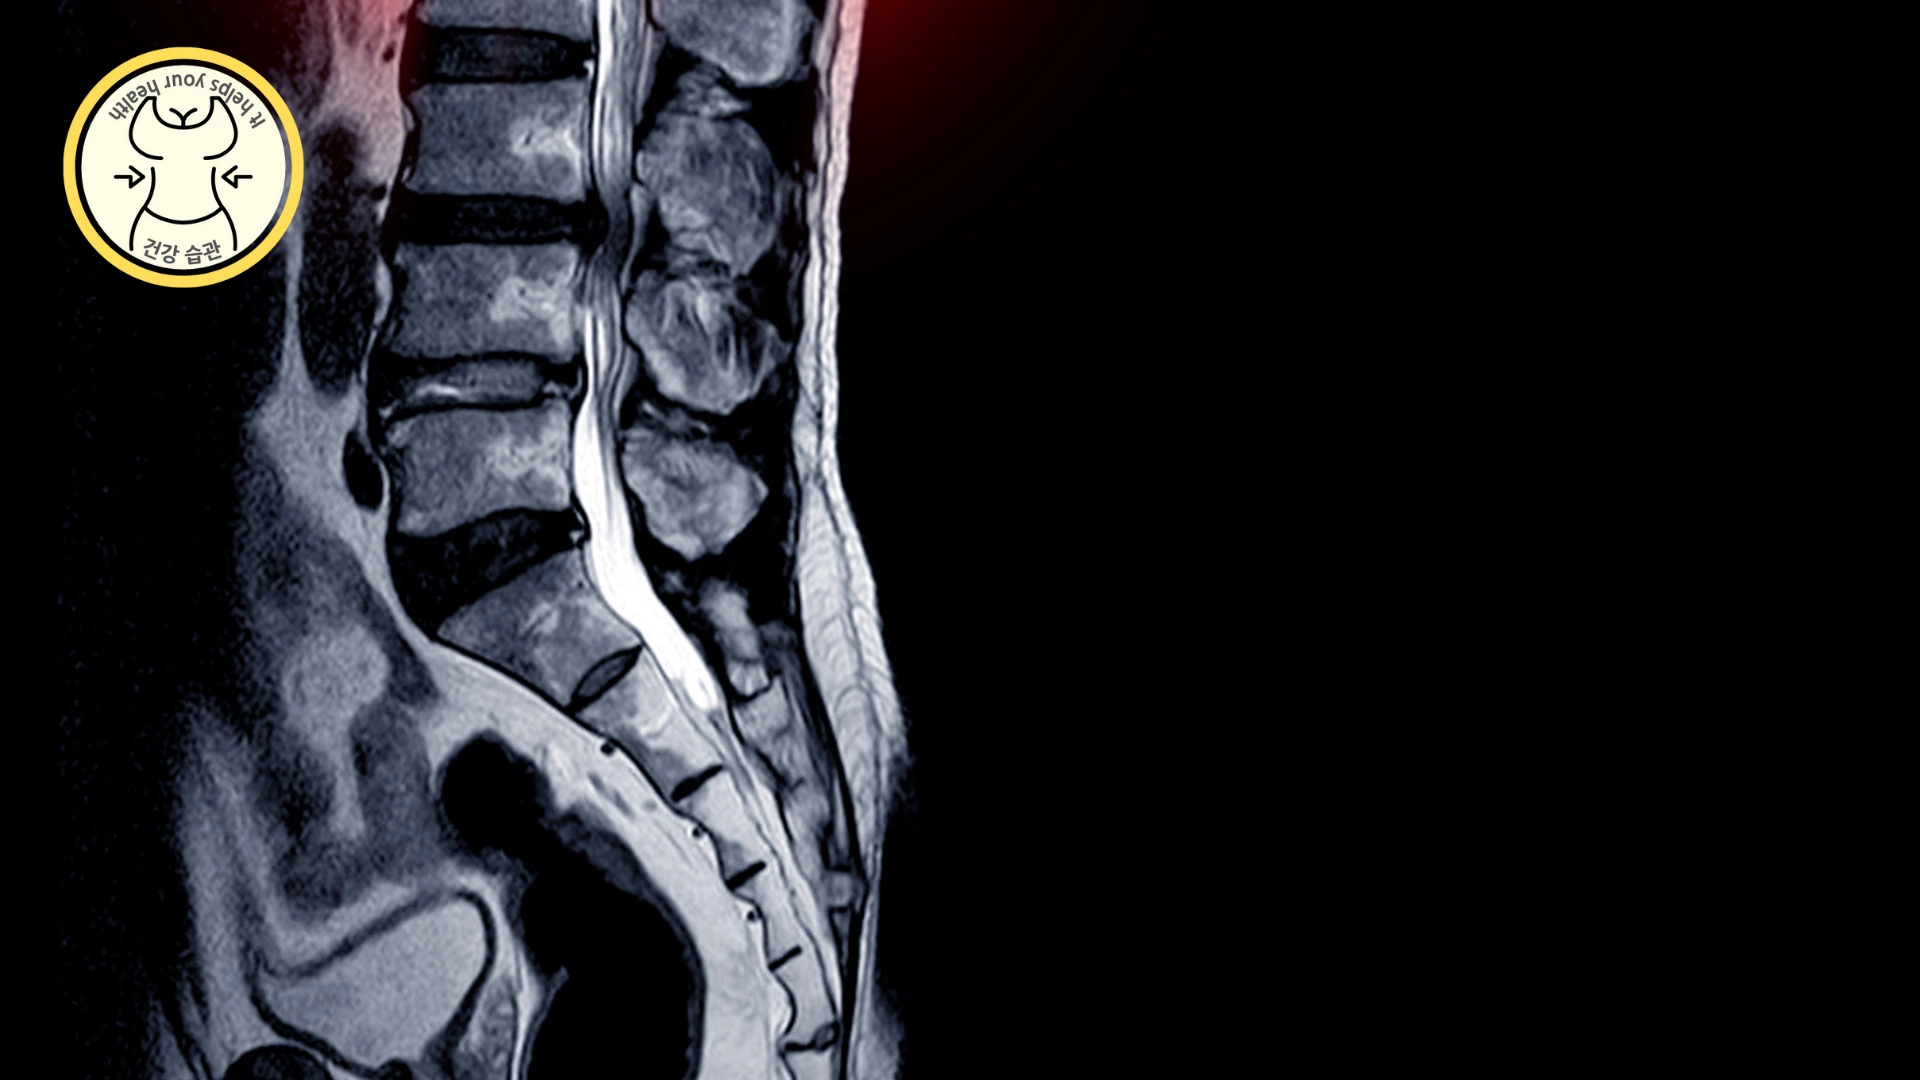

디스크 탈출증

발저림 원인으로 디스크를 의심해 볼 수 있습니다. 척추 뼈 사이에 디스크가 삐져나와 신경을 압박하면서 발 저림이 발생할 수 있는데 한쪽 다리를 들어 올릴 때 45~60도 이상이 올라가지 않고 힘이 빠진다면 디스크 탈출증을 의심할 수 있습니다.

척추관 협착증

척추가 노화되어 뼈가 두꺼워지는데 신경이 지나가는 통로의 척추관이 좁아져 신경이 눌리면 다리가 저리게 됩니다. 이런 경우 발 저림, 발 시림, 허리, 엉덩이 통증의 원인이 됩니다.

협착증이 신경을 누르게 된 경우 수술을 서둘러야 하는데 그 이유는 신경이 눌린 쪽 다리가 힘이 점점 빠지고 근육량도 줄어들어 나중에는 움직일 수 없게 됩니다.

또한 통증으로 인해 허리를 펴지 못하고 굽히고 다니게 됩니다.